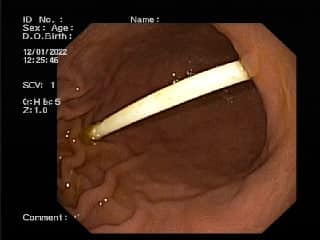

Родителям предложили сделать диагностическую гастроскопию. Поэтому палочку вытянули, она имела длину 8 сантиметров.

В Днепре ребенок съел палочку от конфеты Chupa Chups (facebook.com/groups/Дитячий эндоскопический центр)